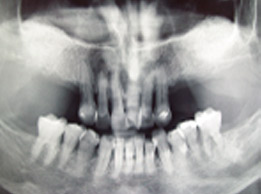

Kirurgija / implantologija